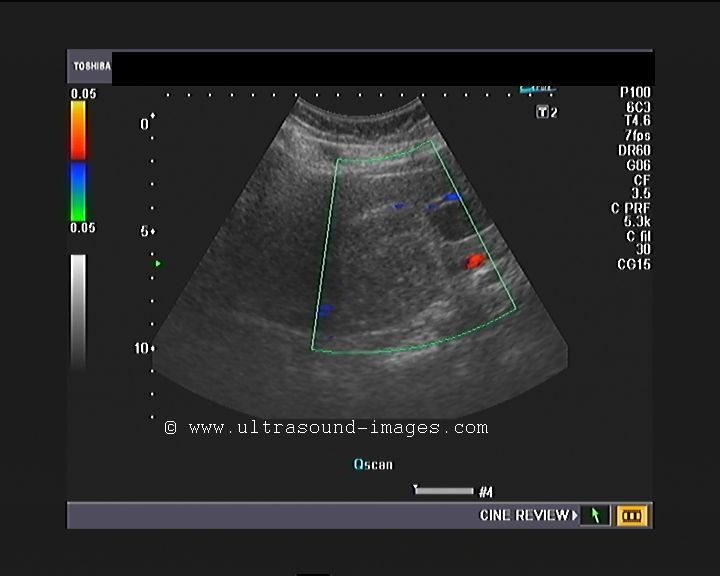

Elongated Left Lobe of Liver (the Beaver Tailed Liver)

Long left lobe of liver (normal variant).

In certain thin individuals (usually seen in thin women), the left lobe of liver appears elongated (see ultrasound images above), and overlies the spleen. In the above pictures, the spleen is seen to be hyperechoic compared to the left lobe (the so called "beaver tailed liver"). Ultrasound images courtesy of Dr. Ravi Kadasne, UAE. The machine used here is the Philips IU 22.